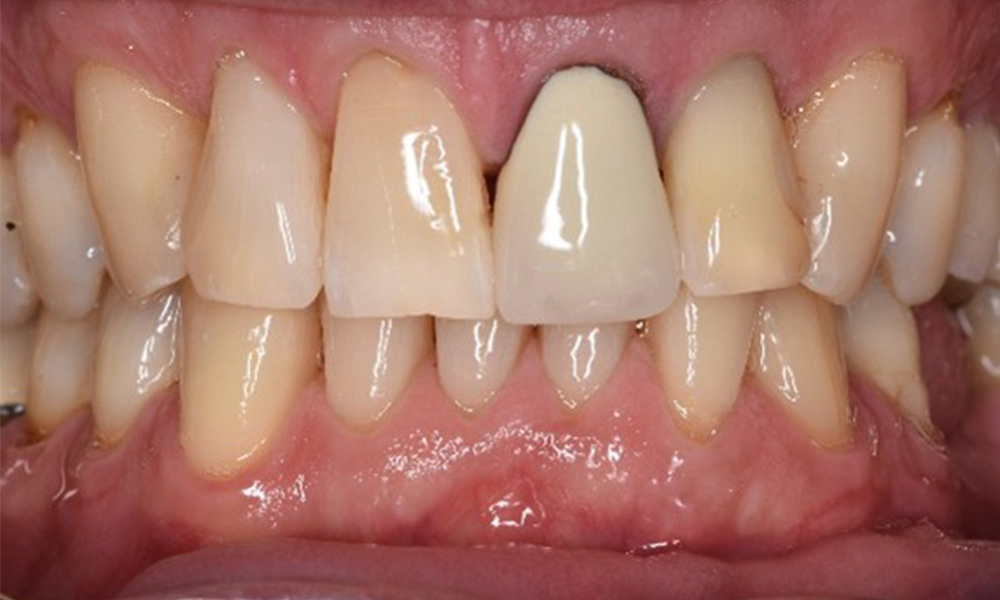

В медицинската история 55-годишният пациент заявява, че няма хронични заболявания и не приема никакви лекарства. Начинът на живот на пациента също е без забележки. Пациентът има няколко зъбни възстановявания и два импланта (2-ри и 4-ти квадрант). Въз основа на настоящите данни се установява гингивит при иначе стабилно пародонтално състояние върху редуцирания пародонт (стадий III, степен А).

Предишни лечения: зъбни възстановявания (съчетание от нескъпоценни метали и керамика), два импланта (2-ри, 4-ти квадрант)